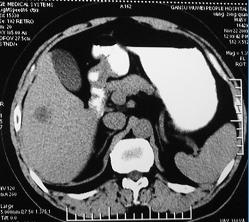

男 45岁。体检b超发现肝脏一低密度病变,怀疑是血管瘤,来ct检查。

ct平扫:在肝右后下叶一直径约2厘米的圆形低密度病变,ct值约32hu。

增强三期都未强化。后经mri检查,t1wi及t2wi为等信号,与肝脏等信号。